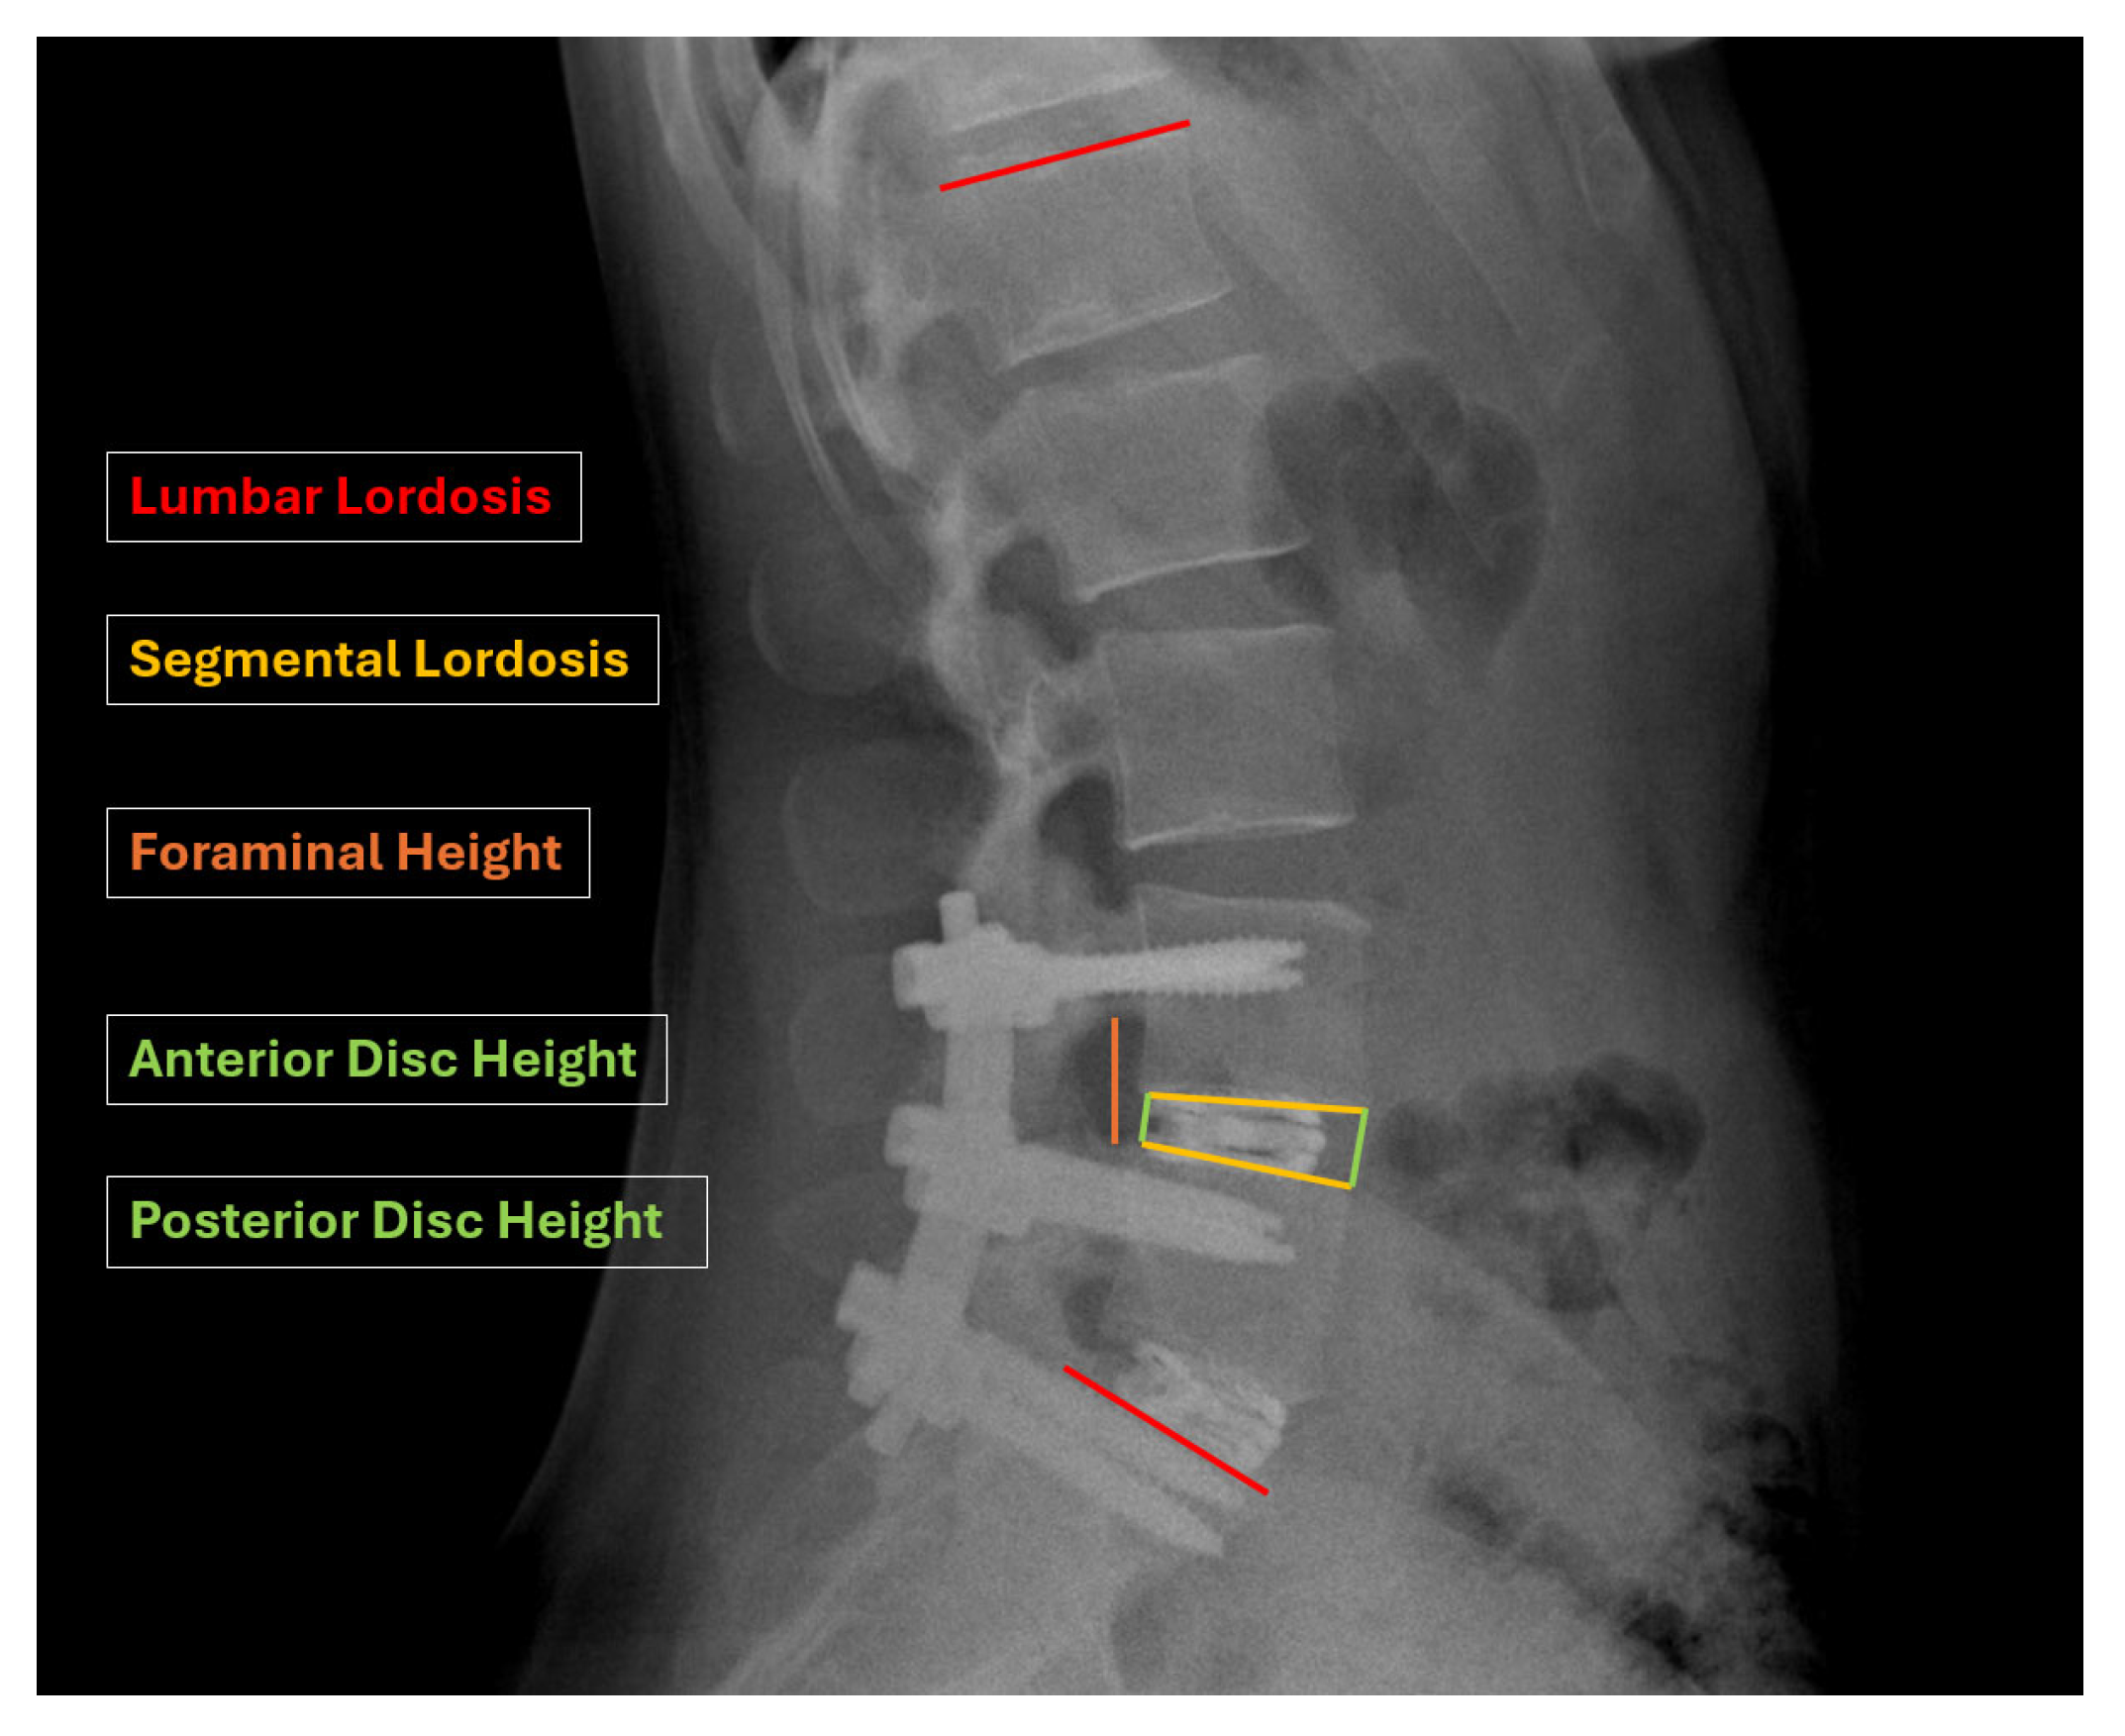

2.3. Radiographic Measures

| Segmental lordosis (°) | 9.0 ± 3.6 | 15.3 ± 3.0 | 15.5 ± 3.0 | 15.4 ± 3.0 | p < 0.001 | p = 0.355 |

| Lumbar lordosis (°) | 41.9 ± 10.5 | 45.7 ± 10.8 | 42.3 ± 11.4 | 41.7 ± 11.6 | p = 0.01 | p = 0.041 |

| Anterior Disc Height (mm) | 5.8 ± 0.5 | 11.3 ± 0.9 | 10.5 ± 1.0 | 9.9 ± 1.0 | p < 0.001 | p < 0.001 |

| Posterior Disc Height (mm) | 3.4 ± 0.6 | 9.3 ± 0.9 | 8.6 ± 0.9 | 8.0 ± 0.9 | p < 0.001 | p < 0.001 |

| Foraminal Height (cm) | 1.0 ± 0.1 | 2.3 ± 0.2 | 2.1 ± 0.2 | 2.0 ± 0.2 | p < 0.001 | p < 0.001 |